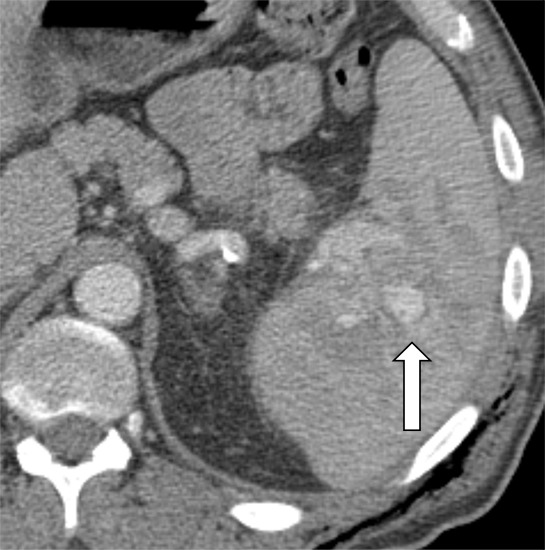

Figure 4a:

Contrast-enhanced CT images show examples of contained vascular injuries (CVIs) and active splenic hemorrhage (ASH). Axial contrast-enhanced CT scans in the (a) portal venous phase and (b) delayed phase in a 56-year-old man after a motor vehicle collision show a CVI in the portal venous phase (arrow), which does not persist on more delayed imaging. Axial contrast-enhanced CT in the (c) arterial phase and (d) portal venous phase in a 51-year-old female pedestrian struck by a car showing a CVI (arrow). (e) Axial contrast-enhanced CT in the portal venous phase 12 hours later shows interval delayed splenic rupture with an intraparenchymal hematoma (*) and surrounding hemoperitoneum (arrowhead). Axial contrast-enhanced CT scans in the (f) arterial phase and (g) portal venous phase in a 26-year-old man after a motor vehicle collision show a large area of ASH (arrow) medial to the spleen (S). Axial contrast-enhanced CT scans in the (h) arterial phase and (i) portal venous phase in a 43-year-old man after motor vehicle collision show multifocal regions of ASH (arrows) on the lateral aspect of the spleen.

Our study engaged members from the American Society of Emergency Radiology to conduct a multi-institutional retrospective study to evaluate factors influencing treatment of patients who sustained blunt splenic trauma (BST) and underwent CT imaging before definitive treatment. Many complex factors are associated with the treatment of patients with BST. Our study aimed to report on practice patterns regarding BST from 11 trauma centers in the United States during the study period and the frequency and clinical impact of CT identification of splenic vascular injuries, among other factors influencing treatment. Two important broad observations were noted. First, a 15.6% increase in treatment with interventional radiology (IR) occurred over the study period, primarily at the expense of surgical treatment (which decreased by 14.8%), for higher-grade injuries. Second, a preference in institutional management of BST was noted (IR management ranged from 5.1% [10 of 198] to 33% [32 of 98] across institutions). Few institutions had higher relative rates of surgical treatment than with IR, whereas others had higher relative rates of IR treatment than surgical. In addition, some institutions had lower rates of patients who were administered only nonoperative management (NOM). CT findings of active splenic hemorrhage (ASH) (adjusted odds ratio [OR], 8.05; 95% CI: 5.35, 12.26; P < .001) and contained vascular injury (adjusted OR, 2.70; 95% CI: 1.64, 4.44; P < .001) were also associated with undergoing invasive treatment (either IR or surgical treatment) versus NOM (Fig 4). CT findings of ASH were also associated with a shorter length of stay in our study (adjusted OR, 0.74; 95% CI: 0.62, 0.88; P < .001).